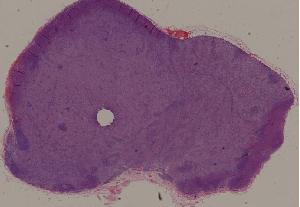

76. Acute pyelonephritis

77. Chronic pyelonephritis

41. Opportunistic infection in the lung

71. Acute transplant rejection of kidney

72. Lupus nephritis

36. Lymphoma

80. Invasive ductal cancer of the breast

84.Graves disease

93. Epidemic cerebrospinal meningitis

94. Encephalitis type B

88. Chronic cavitary tuberculosis of the lung

89. Tuberculous lymphadenitis

90. Lepromatous leprosy of the skin

91. Tuberculoid leprosy

92. Typhoid fever of intestine

95. Poliomyelitis

96. Pulmonary aspergillosis

97. Amebic colitis

98. Schistosomiasis of the colon

99. Experimental acute schistosomiasis of the liver (rabbit)